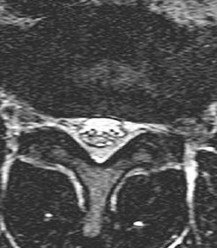

Question 14:

A 72-year-old female presents with bilateral leg and buttock pain that worsens predictably with walking and standing, but improves rapidly when she leans forward over a shopping cart. She has normal palpable peripheral pulses. On advanced imaging, an absolute measurement below what threshold for the anteroposterior (AP) dimension of the lumbar spinal canal is classically diagnostic of absolute spinal stenosis?

Correct Answer: 10 mm

Explanation:

The patient's clinical history is classic for neurogenic claudication secondary to lumbar spinal stenosis. While relative stenosis is typically defined as an AP canal diameter of less than 12 mm, absolute spinal stenosis is defined as an AP canal diameter of less than 10 mm on a mid-sagittal MRI or CT scan.